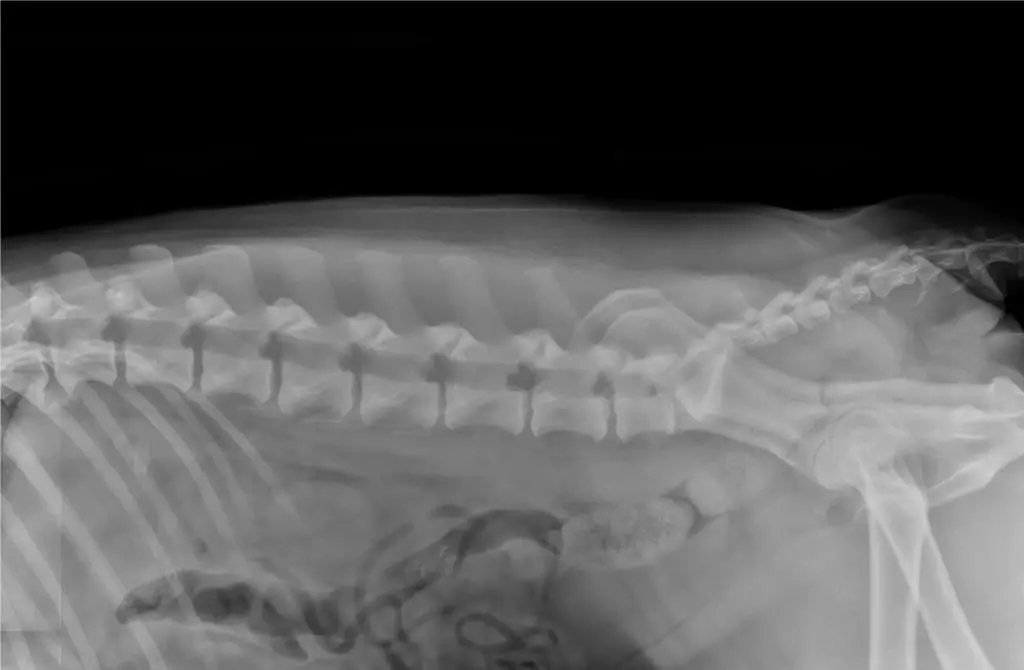

Dysplasie : B cardiopathie : Aso-Pso |